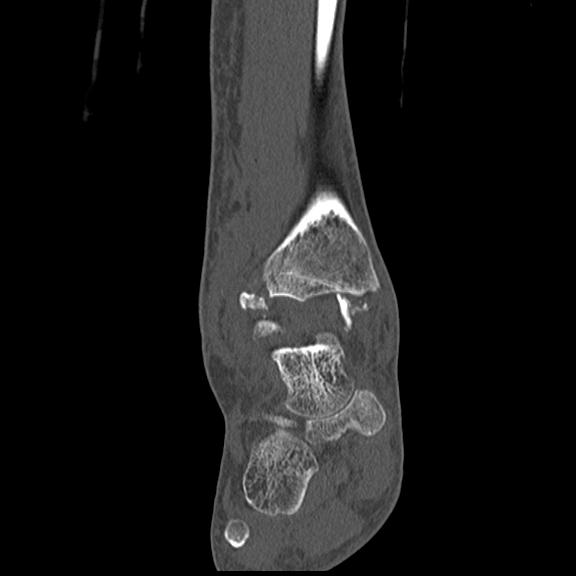

102755 1/4 2R 1/15 2R 右足関節 68歳女性 右三果脱臼骨折